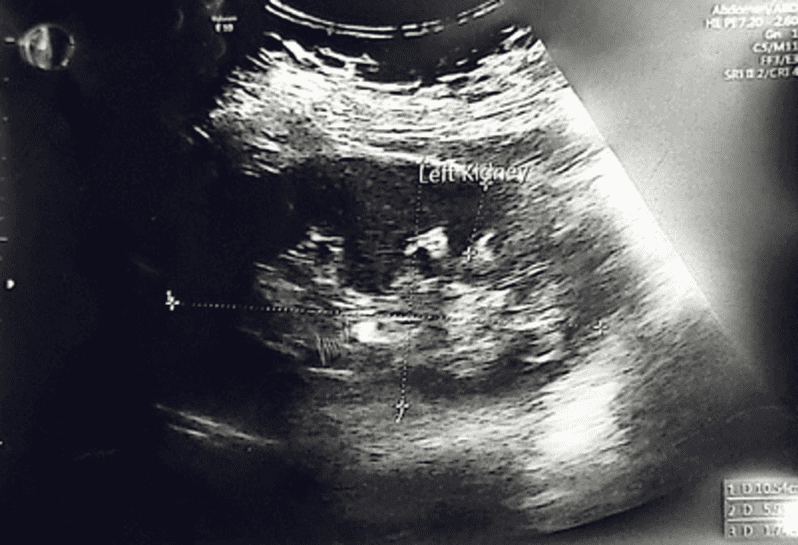

In addition, an abdominal ultrasound done to rule out to any urinary tract obstruction which was normal as shown in Figure 3-5. She was seen by the urology team and advised to keep the urinary catheter until her symptoms improve if not then to keep the Foleys until delivery. The patient was managed conservatively by serial bimanual examinations and an ultrasound was done on a weekly basis until patient condition spontaneously resolved at 13+2 weeks of gestation as shown in Figure 6.

Figure 3: Normal right kidney

Figure 4: Normal left kidney